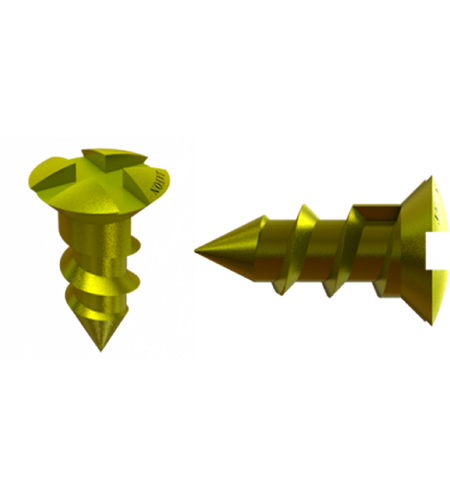

- Requires the use plates and screws are used to attach the patient specific implant to native bone.

Material selection and manufacturing

The material is selected, according to medical and technical aspects; manufacturing is carried out in our modern fabrication centere.